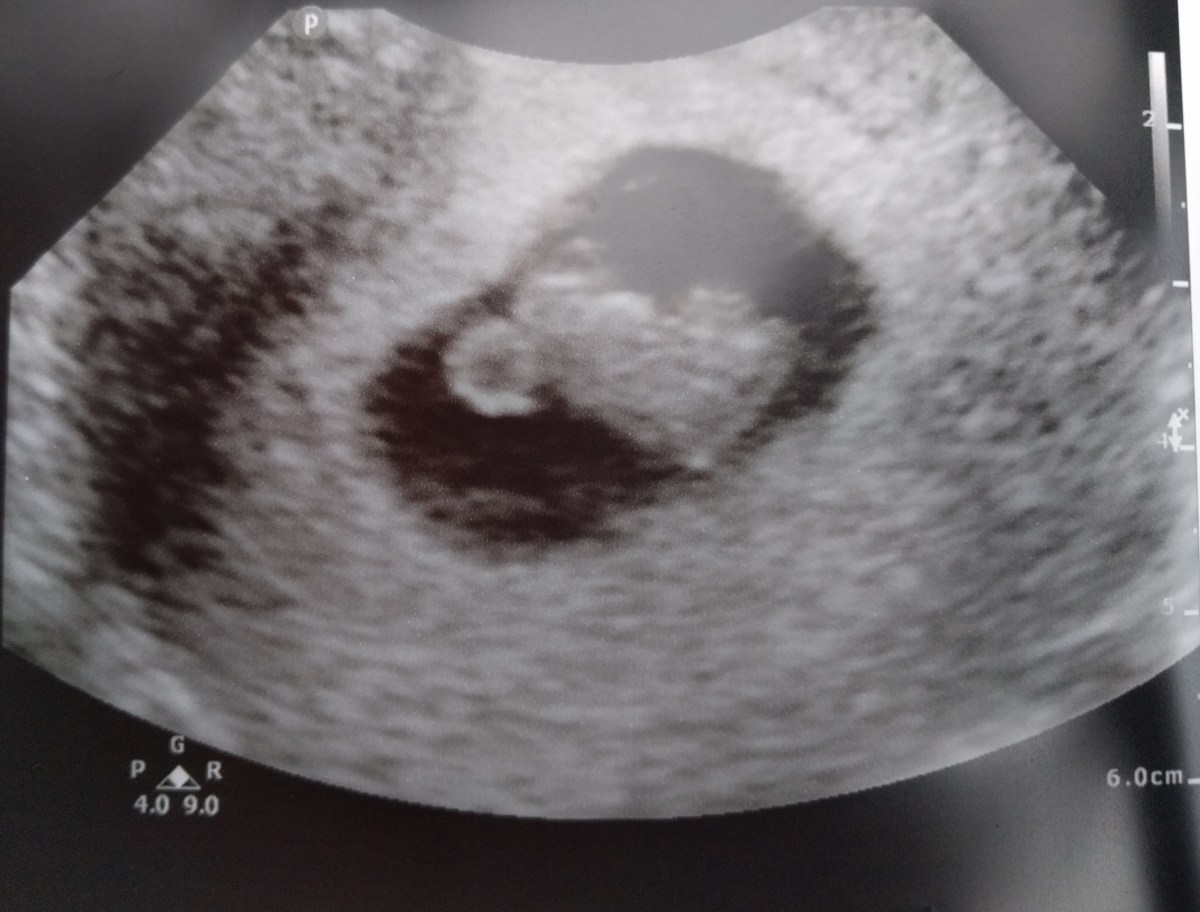

IMG_20171017_172458 Previous Published December 18, 2017 at 3317 × 2523 in Failure and Evolution: Part II